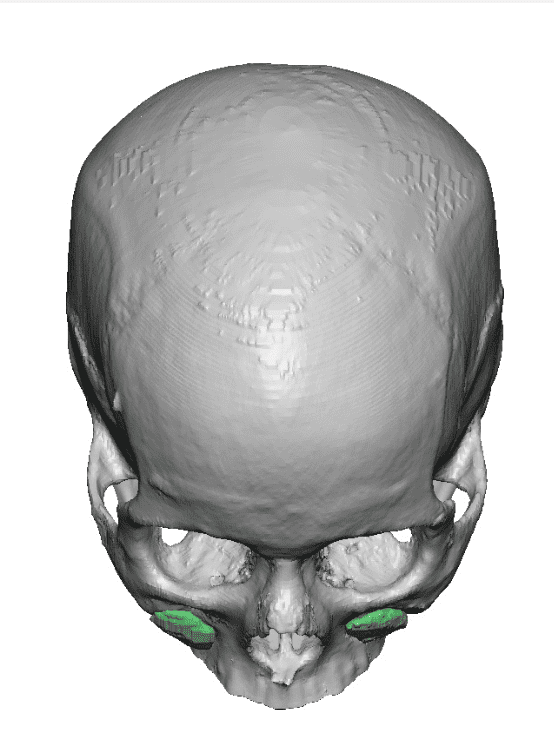

Desire for change of head shape from front view form an inverted V shape to a rounder and wider head shape.

Placement of custom extended forehead-temporal implants through incisions in the crease behind the ear. (he had a prior back of head skull implant which is green in the implant designs and which the head widening implants partially covered it)

Desire for change of head shape from front view form an inverted V shape to a rounder and wider head shape.

Placement of custom extended forehead-temporal implants through incisions in the crease behind the ear. (he had a prior back of head skull implant which is green in the implant designs and which the head widening implants partially covered it)